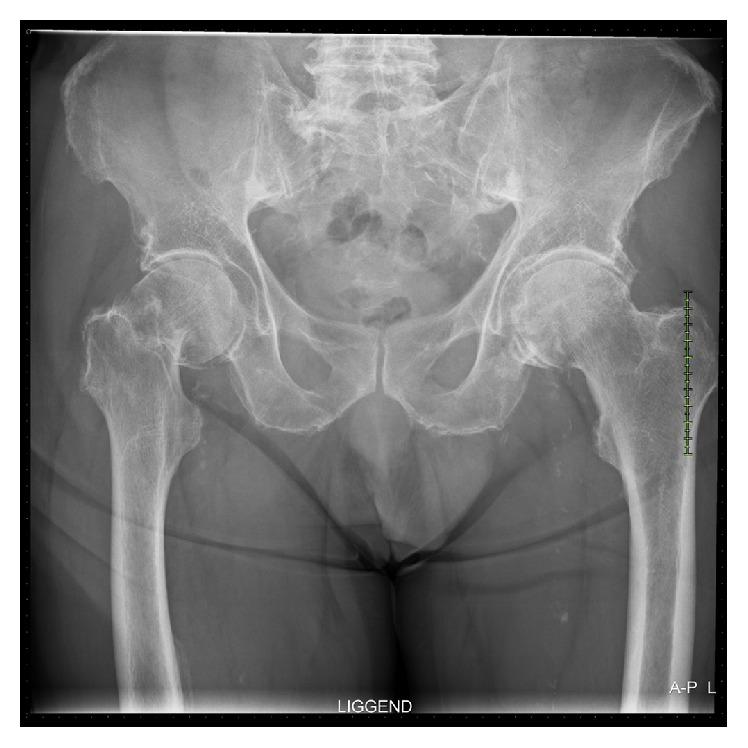

This case report describes a successful two-stage treatment in a 75-year-old male with a displaced neck of femur fracture, also suffering from an active chronic osteomyelitis of the ipsilateral calcaneus. In our case, a below-knee amputation was performed first, followed by total hip arthroplasty two weeks later. At 15-month follow-up, full recovery of the prefracture level of activities of daily living without significant impairment was obtained. Only a few cases of total hip arthroplasty in amputees have been published, but the indication for surgery was mainly traumatic or advanced osteoarthritis. Treating patients with this type of comorbidities is challenging; therapeutic dilemmas can be major. The management in cases like these requires a thorough evaluation and a clear surgical and medical treatment plan, preferably conducted by a multidisciplinary orthogeriatric team.

本病例报告描述了一名75岁男性股骨颈骨折移位且同侧跟骨患有活动性慢性骨髓炎的患者,成功接受了两阶段治疗。在我们的病例中,首先进行了膝下截肢,两周后进行了全髋关节置换术。在15个月的随访中,患者在日常生活活动能力方面恢复到骨折前水平,且无明显功能障碍。目前仅发表了少数几例截肢患者的全髋关节置换术病例,但手术指征主要是创伤性或晚期骨关节炎。治疗患有此类合并症的患者具有挑战性;治疗困境可能很大。对于这类病例的管理需要进行全面评估,并制定明确的手术和医疗治疗计划,最好由多学科老年骨科团队实施。